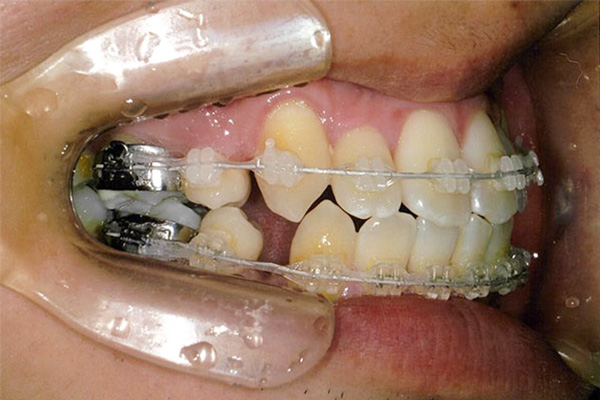

6ヶ月後